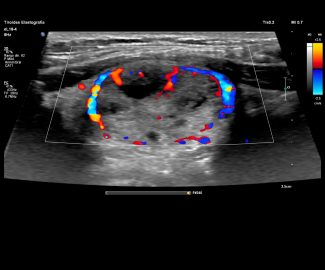

Especialista en diagnóstico por imágenes con más de 25 años de experiencia en el campo del ultrasonido y radiología digital. Trabajamos con equipos de alta tecnología garantizando la calidad y seguridad de nuestros diagnósticos, pues nuestra prioridad es la salud, bienestar y satisfacción de nuestros pacientes.

Sabemos que visitar un centro médico a veces genera nervios. Por eso, hemos creado un ambiente cálido, moderno y 100% seguro para ti. Desde nuestra cómoda sala de espera hasta nuestras áreas de ecografía, mamografía y rayos X, cada rincón está equipado con tecnología de última generación y diseñado para que te sientas en confianza.